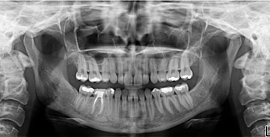

Your first visit to our office typically includes x-rays that allow Dr. Carol to view the structure of the jaw, the position of any teeth that have not yet erupted, malformed roots, and tooth decay. We will also conduct a thorough oral exam, which includes a screening for oral cancer, existing restorations, and a measuring of your periodontal pockets (gums).